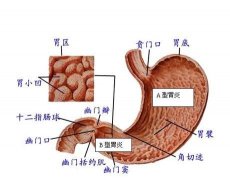

什么叫萎缩性胃炎

导读 萎缩性胃炎是胃黏膜呈慢性浅表性炎症的疾病,为消化系统常见病,属慢

萎缩性胃炎的病因有哪些?如何治疗?

导语 萎缩性胃炎是消化系统常见疾病,据报道:在我国,慢性萎缩性胃炎发病

详解萎缩性胃炎

导语 萎缩性胃炎也称慢性萎缩性胃炎,以胃黏膜上皮和腺体萎缩,数目减少,

什么是慢性非萎缩性胃炎

导语 据先进卫生组织胃病情况统计数据:胃病在人群中发病率高达80%,其中慢